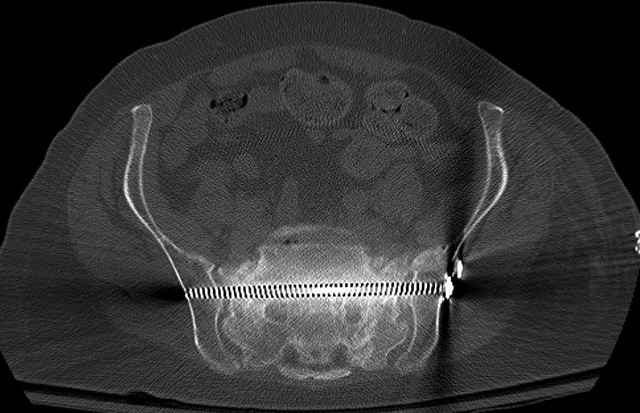

Here are a recent patient’s example slides...

Pelvic CT Scan - 3 Months After Fall

Sacral Injuries

Ramus Fractures

Percutaneous Fixation

(B) Ramus-Retrograde

2 TransIliac-TransSacral

Upper Segment